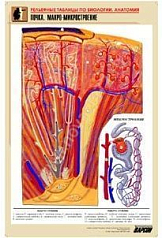

Комплект включает в себя 21 таблицу следующего содержания:

17. Почка. Макро-микростроение;